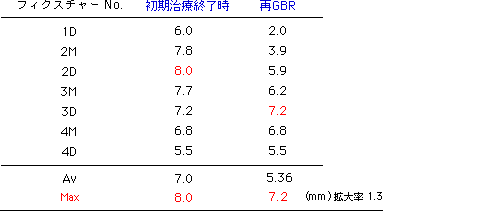

図14:垂直的骨高径の獲得量